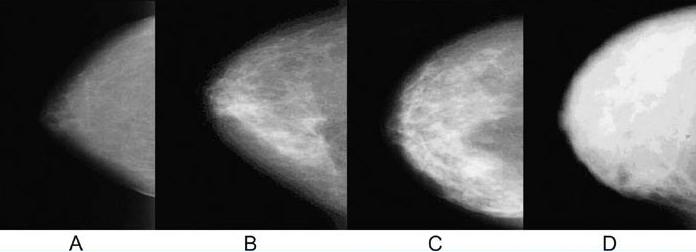

치밀유방(Dense Breast) VS 지방화유방(Fatty Breast)

유방촬영술 상에서 지방조직은 어두운 음영으로 나타나게 되고 유선조직은 하얗게 나타나는데 위 사진에서 보면 왼쪽 A는 하얗게 보이는 유선조직의 분포가 적으며 대체적으로 어두운 음영인 지방조직의 분포가 많은 지방화유방이며 D로 갈수록 유선조직이 풍부해 지며 하얗게 보이는 부분이 넓게 퍼져있는 즉, 유선조직이 조밀하게 뭉쳐있는 분포인 치밀유방이라고 합니다.

동양인들은 서양인들에 비해 유방이 작고 유선조직이 풍부하게 발달되어 치밀유방인 경우가 많은데 이런 경우에는 유선조직에 병변들이 가려 발견이 어려운 경우가 많으므로 유방초음파 검사를 받아보시는 것이 좋습니다.